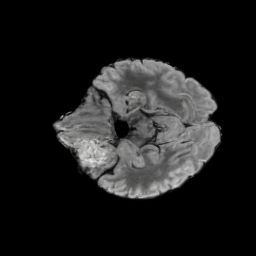

Brain Volumes Preservation. The generated MRIs by our X-Diffusion retain almost the exact same average brain volume vs. of the real MRIs.

Tumour Information Preservation. For the brain tumor segmentation, we use a Swin UNETR model[28, 70], trained with random rotation, and intensity as data augmentation. On the test set with human ground-truth annotations (), the brain volumes generated from single slice input preserve the volume of the different tumour components (paired t-test, for all 3 classes). In Figure 4, we highlight the tumor profiles of the generated MRIs compared to the ground truth tumour profile. The real MRI Dice score in the test set is 85.15 while the generated MRIs from a single slice have a dice score of 83.09. This shows how the generated MRIs indeed preserve the tumor information and can act as an affordable and informative pseudo-MRI, before conducting an actual costly MRI examination in hospitals. More detailed results are provided in supplementary material.

The comparison of generated MRIs versus reference MRIs suggest a nearly perfect preservation of brain volume (in mm3) with median volume of reference MRIs of versus generated MRIs (see an example of brain generation in Figure II).

On the test set with human ground-truth annotations (), the brain volumes generated from single slice input preserve the volume of the different tumour components (paired t-test, for all 3 classes) (see Table I). The real MRI Dice scores are put for reference to our generated MRIs. X-Diffusion outperforms baselines TPDM [39] and ScoreMRI [19] in tumour preservation (see Table I and Figure III). We ran experiments comparing the tumour segmentation Dice Score varying X-Diffusion configurations. The multi-slice input X-Diffusion achieves marginally better Dice Score than the single slice input model (83.47 83.09). We also ran experiments with slice input used for volume reconstruction intersecting or not with tumour. We observe on average a drop of 6% Dice Score (see Table I). Further away from the tumour the input slice for volume reconstruction is selected, we observe a linear decrease in tumour segmentation Dice Score with lowest value of 77.21 Dice Score (see Figure VI).